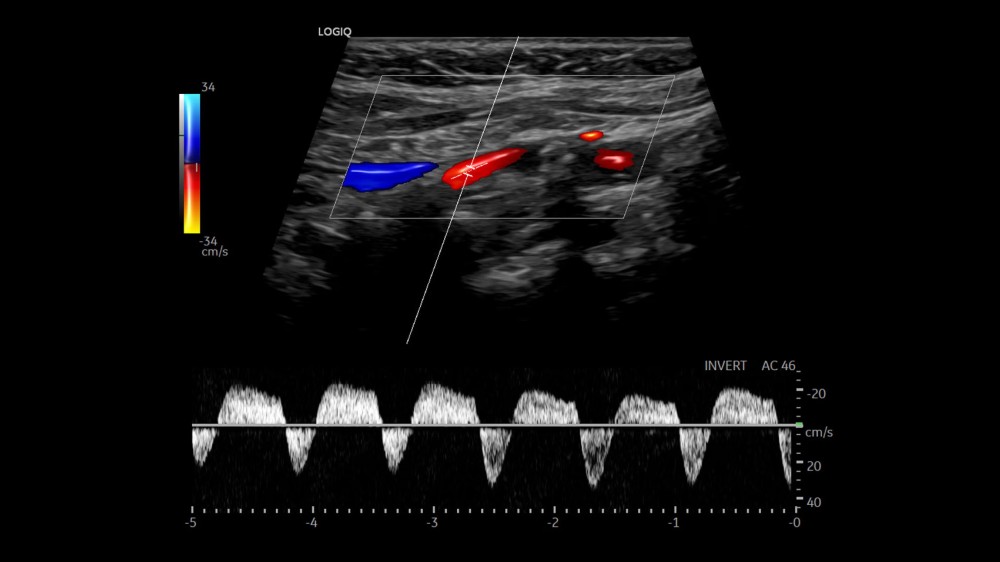

MVI (Micro Vascular Imaging): Kiçik damarların yüksək dəqiqlikli qiymətləndirilməsini təmin edən mikro-damar görüntüləmə rejimi.

Radiantflow™: Kiçik damarların üçölçülü vizuallaşdırılmasını təmin edən texnologiya, MVI ilə birlikdə istifadə edildikdə damar morfologiyasının təhlilini asanlaşdırır.